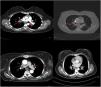

ResultsAmong 109 patients, eighty-one patients CXR and CT imaging taken at the same radiology center has been reached. Demographic, radiological, and clinical data of 81 patients were obtained from a total of 109 patients, and the record data of these 81 patients were evaluated. Patients who could not be reached for all tests were excluded from the study. Among 81 sarcoidosis patients 23 (28.4%) were male, 58 (71.6%) were female. The mean patients age was 46.4 years and the mean disease duration was 3.8 years (Table 1). As for system and organ involvement; arthritis was seen in 62 (76.5%), Löfgren's syndrome in 13 (16%), erythema nodosum in 32 (39.5%) patients, uveitis in 10 (12.3%) patients, myositis in 1 (1.2%) patient, and neurosarcoidosis in 1 (1.2%) patient. In laboratory tests, increased serum levels of angiotensin-converting enzyme (ACE) were detected in 42 (51.8%) patients, serum calcium in 7 (8.6%) patients, and serum vitamin D3 in 1 (1.2%) patient. As for the acute phase reactants, increased C-reactive protein (CRP) level was detected in 38 (46.9%) patients and increased erythrocyte sedimentation rate (ESR) in 41 (50.6%) patients. Among 81 patients, CXR is regarded as normal at diagnosis in 30 (37%) patients, while all of these patients had findings consistent with sarcoidosis on CT imaging. Eighty-one patients which have findings consistent with sarcoidosis on CT examination were as follows: stage 1 (bilateral hilar lymphadenopathy) in 52 (64.2%) patients, stage 2 (bilateral hilar lymphadenopathy+pulmonary infiltrate) in 20 (24.6%) patients, stage 3 (only pulmonary infiltrate without hilar lymphadenopathy) in 6 (7.4%) patients, and stage 4 (pulmonary fibrosis) in 3 (3.7%) patients with sarcoidosis (Table 2). Regarding disease stages, CT imaging detected more patients with stage 1 and stage 2, compared with other stages of disease (p=0.02, p=0.04 respectively) (Table 3). When compared with CXR, CT imaging was more superior in the detection of early diagnosis and stage determination of sarcoidosis (p=0.001). One patient had pleural involvement and another one had suspected pulmonary hypertension (PH) detected on CT imaging while CXR was normal in these patients both. CT imaging was more superior for early detection of disease extent and complications, such as pleural involvement, PH, micronodules and active alveolitis. The most frequent findings detected on CT examination were bilateral symmetrical hilar and mediastinal lymphadenopathy, micro and macronodules, located along bronchovascular bundles, interlobular septi, interlobar fissures, and in the subpleural region. In patients with stage 4 the features of alveolitis/fibrosis including “ground-glass” and “honeycombing”, architectural distortion, and traction bronchiectasis were seen. Most frequently, lesions in sarcoidosis demonstrate predilection to the upper and middle fields. There were not found correlation between CT findings and lung function tests (p=0.45).

CXR-based staging of sarcoidosis was developed before the introduction of CT, and for decades, it has been the gold standard for staging, follow-up and prognosis of pulmonary sarcoidosis.14 It was preferential method because of low price, low radiation exposure and wide use as well. However, the intensity of symptoms, the presence of extrapulmonary disease, the results of pulmonary function tests, and the necessity of treatment are not well correlated with CXR.15 CXR is insufficient to portray small parenchymal abnormality in early stages of the disease, and small mediastinal and hilar lymphadenopathies. The study showed that there was no correlation between lung function tests (FVC, FEV1 and DLCO) and CXR imaging and it is not a reliable test to detect pulmonary exacerbations of sarcoidosis.16 CT scans are more sensitive than CXR in detecting lung parenchymal changes in sarcoidosis. High-resolution CT (HRCT) can reveal ground-glass opacities, nodules, and peribronchovascular thickening. CT can help in assessing disease extent and severity, guiding treatment decisions, and monitoring disease progression. Unlike X-ray scans, some CT lesions demonstrate a relationship with pulmonary function tests.17 Drent et al. demonstrated correlations between respiratory functional tests and CT features such as thickening of the bronchovascular bundle, intraparenchymal nodules, septal and non-septal lines, or focal pleural thickening.18 Zappala et al. have suggested that compared with CXR presentations, CT scan appear to be more consistent with pulmonary functional changes.19 CT is significantly more sensitive than CXR regarding detection of early sarcoidosis lesions, which may help us for early decision treatment. This is true even in stage 1/2, which is linked with a favorable long-term prognosis. Despite these facts, the predictive significance of CT findings has not yet been subjected to a significant amount of research. Even among chest radiologists, there is considerable heterogenicity and subjectivity in the interpretation of CXR. Baughman et al. evaluated the discrepancy between two chest radiologists initial assessments of Scadding staging using data from a clinical trial.20 Overall, the authors discovered only fair interobserver concordance, and with regards to the presence of fibrosis, they found only fair interobserver concordance. They also mentioned that it was hard to tell if a patient was at stage II or stage III because chest radiologists could not agree on the appearance of hilar lymphadenopathy. Zhang et al. compared the chest CT and CXR imaging for staging of pulmonary sarcoidosis using clinical records of 227 sarcoidosis patients.21 They reported that overall, 50.2% patients showed discordant sarcoidosis stage between CXR and CT, which findings support the results from our present study. The primary reason for inconsistent stage between CXR and HRCT was failure to detect mediastinal lymph node enlargement in the shadow of the heart in CXR and small nodules because of the limited resolution of CXR. Also they found more patients with pleural involvement detected by CT (25.6%) compared with CXR (7.5%). In addition, the authors recommend new staging criteria for pulmonary sarcoidosis according to CT imaging, not CXR. Russo et al. investigate the sensitivity and specificity of different chest imaging for sarcoidosis screening in patients with cardiac presentations.22 While the CXR was suboptimal as a screening test, in contrast CT and cardiac/thorax MRI had excellent sensitivity. CT has the highest specificity among imaging modalities. Sarcoidosis primarily affects the upper lung zones, and granuloma are predominantly spread along lymphatics, it is more difficult to assess these regions using CXR and when assessing lesions of this kind, CT is preferable method. CT may also distinguish confluent granulomas, which have a peculiar imaging result known as the “galaxy sign,” which resembles a star cluster when viewed through a telescope.23 CT also may help in the differential diagnosis of sarcoidosis with lymphangitic carcinomatosis, which can present with a nodular perilymphatic pattern and septal thickening. Various studies have demonstrated the superiority of CT in detecting lesions corresponding to fibrosis and in diagnosing more advanced stages of the disease.24 CXR scans revealed fibrosis in 5–10%, whereas CT scans resulted in such changes being described in as many as 20–50% of patients. In fibrotic stage, the presence of “honeycombing” and traction bronchiectasis is associated with worse prognosis, and a larger degree of fibrotic alterations detected on CT scan is known to be predictive of mortality.25 Our research results align with previous studies in the literature. In this investigation, we observed that CT imaging outperforms CXR in terms of early detection and staging of sarcoidosis (Fig. 1). The predominant stages identified through CT examination, which were not visible on CXR, were stage 1 and stage 2 (Fig. 2). Furthermore, CT imaging provided valuable insights into pleural involvement, early alveolitis, and pulmonary hypertension.25 Nevertheless, our study does have certain limitations. Firstly, the data we used was confined to a single center and involved a relatively small number of patients, which restricts the generalizability of our findings to all sarcoidosis patients. Another limitation is that our study population consisted solely of individuals of Caucasian origin, and it is widely acknowledged that disease phenotypes may exhibit significant racial differences. Consequently, it is essential to replicate our findings in a group of African-Americans to ensure their broader applicability. Furthermore, had we enrolled patients consecutively and conducted a prospective evaluation of CXR and CT scans with a larger number of readers, it would have likely minimized potential biases in the results. Despite these limitations, it is worth noting that our findings align closely with those reported in existing literature on the subject.